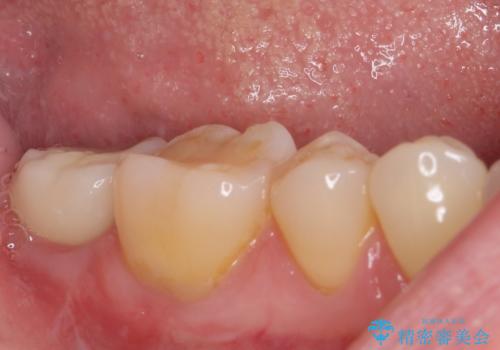

抜歯されたままの奥歯 ストローマンインプラントによる欠損補綴治療

- 抜歯してから放置されている右下の奥歯へのインプラント治療を希望して来院された患者様です。

ストローマン社のSLActiveというインプラントを使用し、インプラント埋入からクラウンが装着されるまで3ヶ月弱という短期間で終えることができました。

咬み心地はもちろん、清掃性もご自分の歯とほとんど変わらない状態となり、患者様には大変満足していただきました。